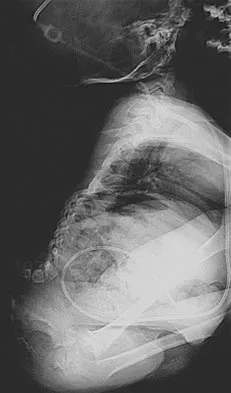

Figure 11 shows the anatomic dissection of the medial side of the knee joint after removal of the superficial fascia. The arrow is pointing to what structure?

Options:

- Semitendinosus tendon

- Gracilis tendon

- Sartorius tendon

- Semimembranosus tendon

- Medial collateral ligament

Correct Answer: Semitendinosus tendon

Explanation:

The semitendinosus and gracilis tendons lie beneath the superficial fascia and superficial to the medial collateral ligament. The semitendinosus is located more inferior to the gracilis tendon. The sartorius is more posterior and distal as is the medial collateral ligament. The semimembranosus is posterior. Pagnani MJ, Warner JJ, O'Brien SJ, Warren RF: Anatomic considerations in harvesting the semitendinosus and gracilis tendons and a technique of harvest. Am J Sports Med 1993;21:565-571.